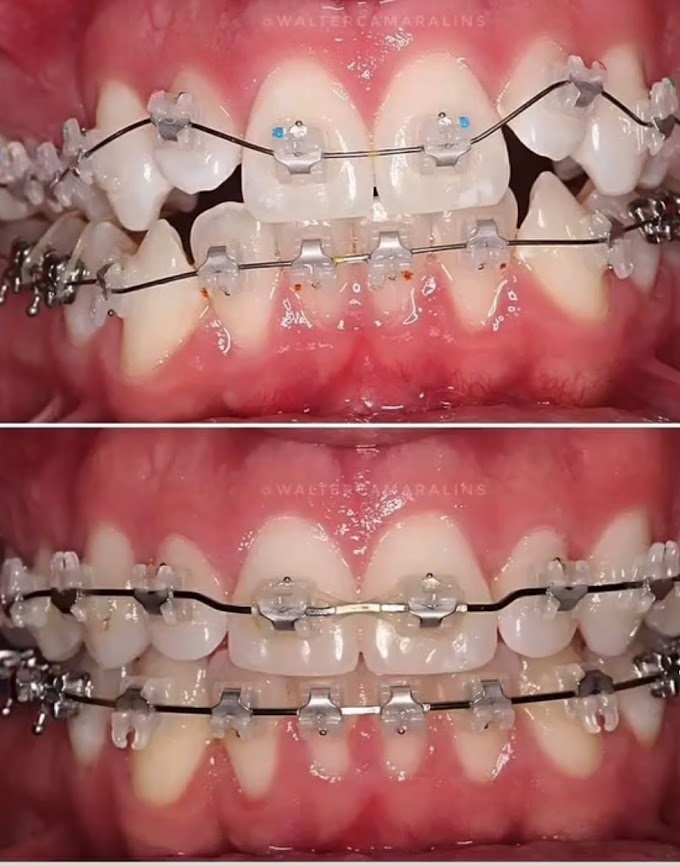

visit:fixedbraces